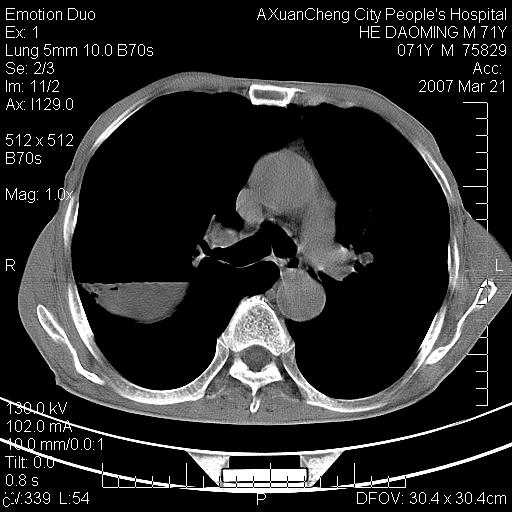

标题: CT7269:[原创] 咳嗽,咳痰,大家讨论右肺病变的部位 [打印本页]

标题: CT7269:[原创] 咳嗽,咳痰,大家讨论右肺病变的部位

1.慢支肺气肿 肺心病 肺大泡;2.叶间裂积液,前胸膜粘连

右侧相当于叶间软组织样密度ct值约50hu,请大家讨论是什么性者病变

考虑:慢性支气管炎合并全小型肺气肿、肺大泡、间质纤维化、感染,右斜裂积液。

考虑慢支,肺气肿,肺大泡,间质纤维化;右侧斜裂液气胸考虑(可能因为肺大泡破裂破入斜裂所致).

1双肺慢性支气管炎并全小叶型肺气肿肺大泡2间质性纤维化3右侧斜裂积液

考虑:慢性支气管炎合并右侧全小型肺气肿、肺大泡并感染、双肺间质纤维化,右斜裂积液。